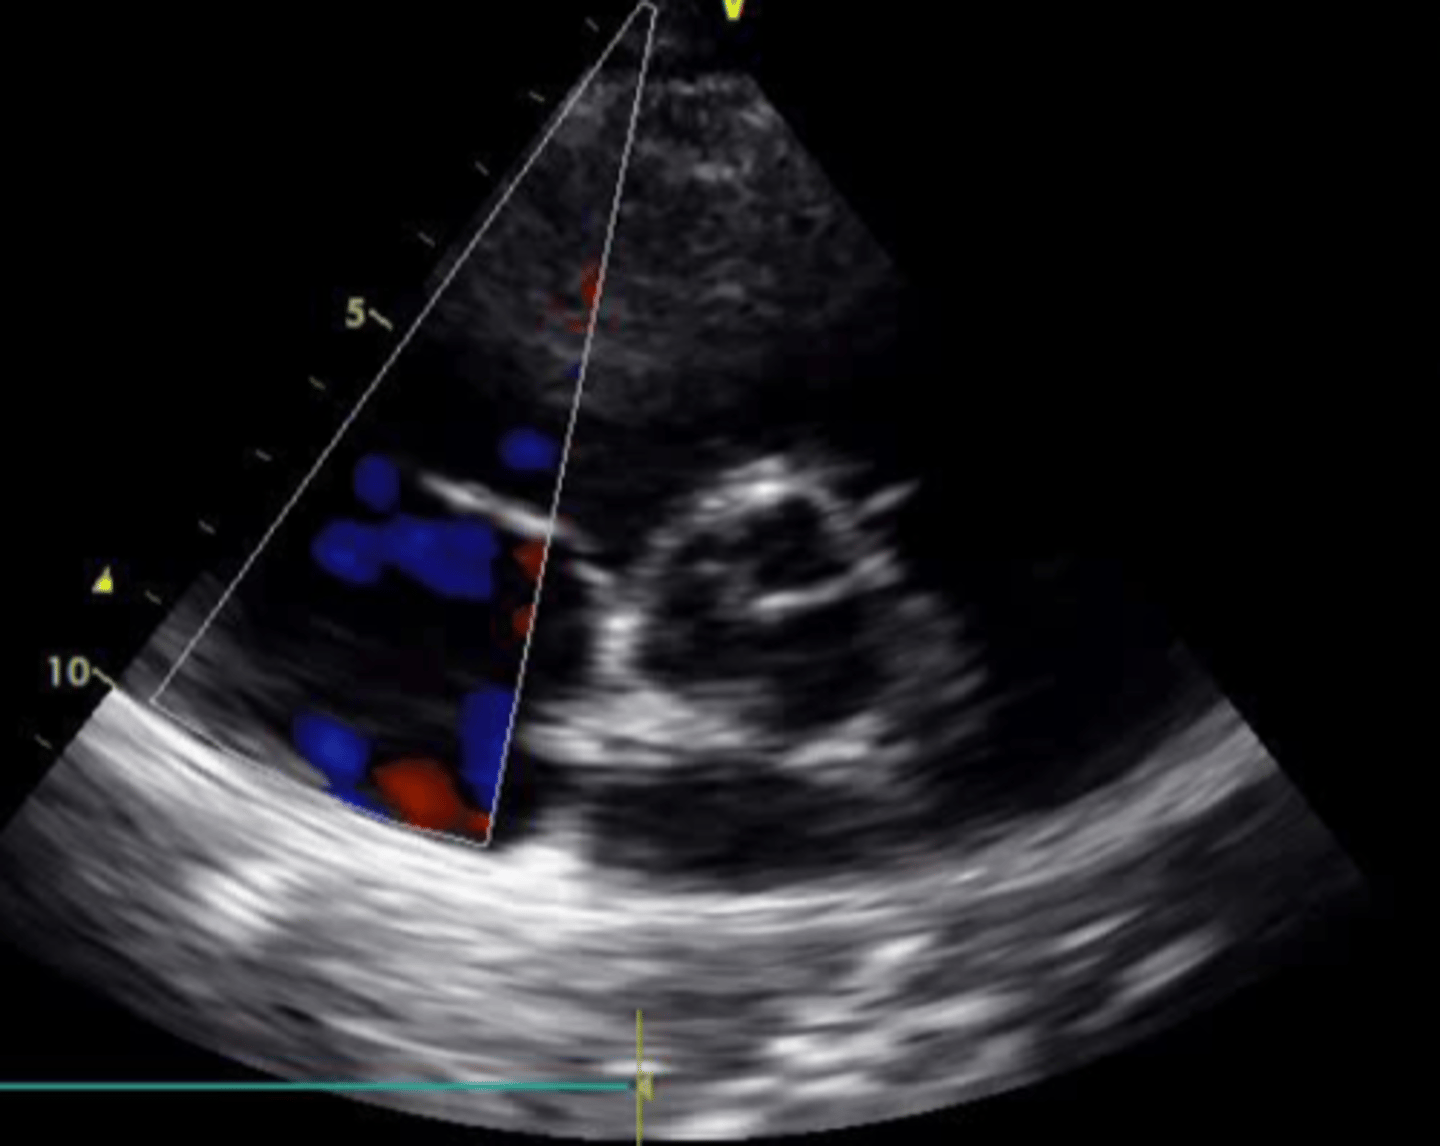

anterior tricuspid valve leaflet

left leaflet

medial/septal tricuspid valve leaflet

right leaflet

anterior mitral valve leaflet

left leaflet

posterior mitral valve leaflet

right leaflet